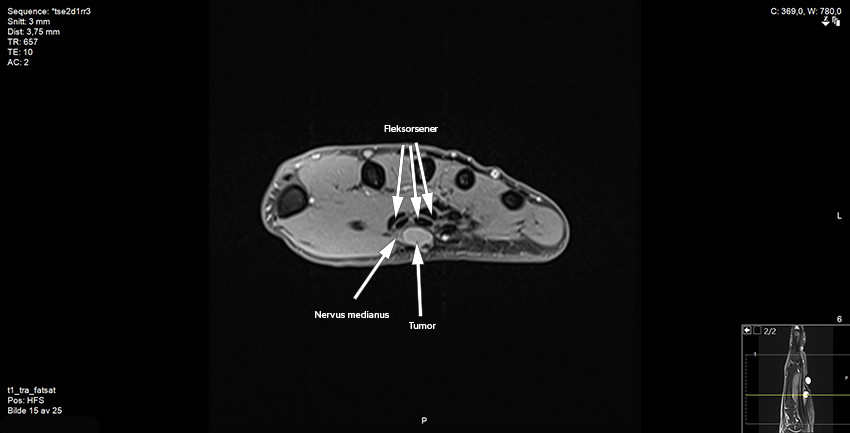

Pasienten ble deretter henvist til MR-undersøkelse ved privat klinikk og videre til ortopedisk avdeling ved regionsykehus. Etter MR-undersøkelsen beskrev radiologen en kontrastladende, velavgrenset bløtdelstumor like ved eller på nervus medianus ved utgangen av karpaltunnelen. Konklusjonen var at tumor var forenlig med et scwhannom, men at annen tumor ikke kunne utelukkes (figur 2 og 3).

Pasienten var plaget av kulen og ble tilbudt operasjon i narkose. MR-bildene ble forevist radiologer ved regionsykehuset. Arbeidsdiagnosen var et schwannom i relasjon til nervus medianus. Etter å ha spaltet karpalligamentet kom vi inn på tumor, som lå på medianusnerven der den forgrener seg utover i hånden. Tumor var ca. 10 × 10 mm og velavgrenset, og lot seg fridissekere fra nerven med unntak av den motoriske thenargrenen, som gikk tvers gjennom tumor og måtte reseseres. Nervegrenen lot seg sy uten behov for nervegraft. Makroskopisk syntes vi tumor liknet mest på et schwannom, men på grunn av innvekst i nerven var nevrofibrom en nærliggende differensialdiagnose. Vevspreparat ble sendt til histologisk analyse.

Pasienten ble umiddelbart informert om biopsisvaret og henvist til sarkomsenter. De preoperative MR-bildene ble gransket på ny av tumorradiologer. De konkluderte med at det var solid vaskularisert tumor langs nervus medianus og ikke noe typisk «target sign» eller «fascicular sign», som ofte ses ved benigne nerveskjedesvulster. Noen mer presis diagnose kunne ikke stilles basert på de preoperative MR-bildene. CT toraks, CT abdomen og ultralyd av glandler i aksillen viste ingen tegn til metastaser. Ny MR-undersøkelse av hånden viste ingen tumorrest. På grunn av tumors beliggenhet tett på stor nerve og sener ble ikke utvidet reseksjon anbefalt. Pasienten ble gitt postoperativ strålebehandling, 2 Gy × 30, for å minske risikoen for lokalt residiv. Ved siste kontroll hadde sårene etter strålebehandlingen tilhelet. Pasienten hadde ingen plager med nervesmerter og ingen nerveutfall.